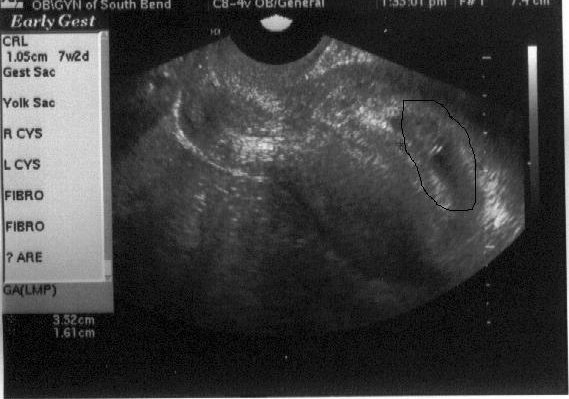

| As you can tell, there's really not much to see yet. In the circle I drew on the right-hand side of the picture, however, you should be able to see two white lines. Those two white lines mark off where the flickering little heartbeat is, and that's pretty exciting! Click here to read about the day we had this ultrasound done. (April 11, 2002 - 7 weeks, 2 days) |